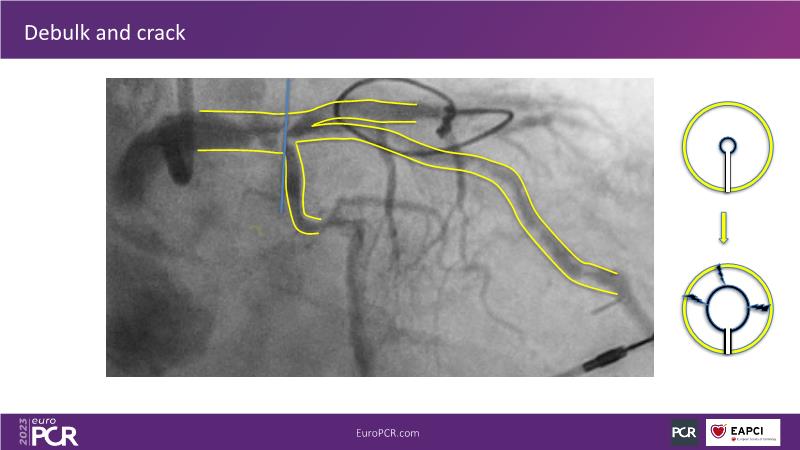

The aim of this session is to address the question of how to optimise outcomes for high-risk patients by analyzing two real-life cases for discussion: a distal calcified left main trifurcation and a high-risk PCI with orbital atherectomy.

- To learn how the distinct attributes of orbital atherectomy (OA) may help you address challenges in heavily calcified vessels